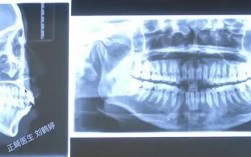

“正畸过山车”并不是一个标准的医学术语,而是患者和医生之间在描述牙齿矫正(正畸)治疗过程时,一个形象生动的比喻,它指的是正畸治疗过程中那种充满起伏、波动、有时甚至让人感觉刺激或不适的体验**,“正畸过山车”主要包含以下几个层面的含义:身体感...